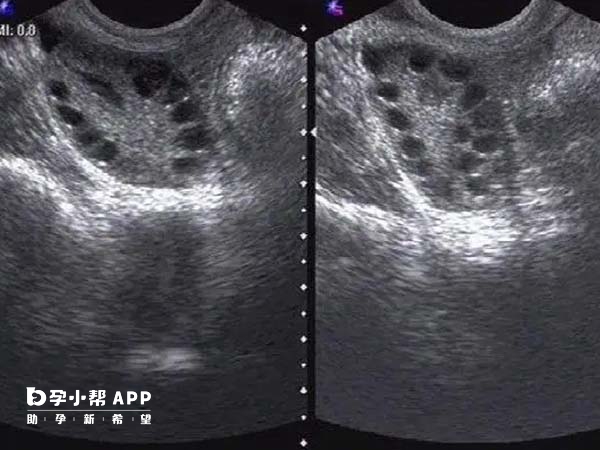

凍胚和鮮胚移植對於試管患者來說並不陌生,其實它倆在手術操作上基本相似,只是影響凍胚移植成功率的關鍵因素是如何把握胚胎髮育和子宮內膜的同步化,而此環節中比較重要的是何時排卵,以下是“移植凍胚為什麼要等卵泡排出來”的相關介紹:

一般來說,如果患者在凍胚移植期間使用的是半自然週期,那麼是需要先等卵泡排出來的,卵泡要是沒有排掉,移植成功率可能會降低,因為移植凍胚前要根據排卵時間來推測子宮內膜接受期,從而確定凍胚移植時間,保證胚胎與子宮內膜發育同步,由於排卵後內膜、激素等各項指標都比較適宜,這時進行移植能大大提高試管嬰兒妊娠率。